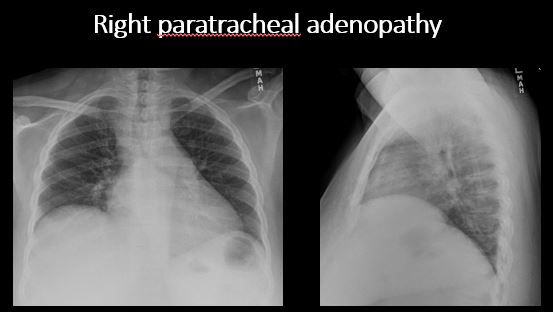

Section 1 Submit Findings Case322 Findings Technique The exam is expiratory, rotated, over or under penetrated, or limited by overlying structures or soft tissues, body habitus, patient positioning, or motion. Yes No Support Devices There is a vascular line or lines present in an abnormal location or otherwise abnormal. Yes No There are other devices such as a chest tube or pleural drain, feeding, NG, or gastrostomy tube, LVAD or pacemaker, vascular stents, cardiac valves, anesthesia catheter, VP shunt, neurostimulator, or other drains or tubes present that are in an abnormal position or are otherwise abnormal. Yes No Cardiomediastinum The superior mediastinum is abnormally widened considering the technique. Yes No There is abnormal shift of the mediastinum. Yes No There is a mass or other abnormal density in or overlying the mediastinum. Yes No There is an abnormality in the retrosternal, retrotracheal, or retrocardiac space on the lateral view. Yes No There is abnormal tracheal deviation or narrowing on the frontal and/or lateral view. Yes No There is pneumomediastinum and/or pneumopericardium. Yes No There is enlargement of the cardiac silhouette. Yes No The heart borders are abnormal. Yes No The right paratracheal stripe is thickened or enlarged. Yes No The azygoesophageal recess is displaced or otherwise obscured. Yes No Vasculature and Hila The aorta is dilated, tortuous, ectatic, calcified, or there is a focal contour abnormality. Yes No The central pulmonary arteries or hila are enlarged. Yes No The aorto-pulmonary window is convex or obscured by a mass, adenopathy, or vasculature. Yes No There is cephalization or haziness of the pulmonary vessels or congestion of the central pulmonary vasculature. Yes No Lungs The lungs are hyperinflated or underinflated generally or segmentally. Yes No There is focal, multifocal, or diffuse airspace disease, mass, opacity, or nodularity. Yes No There is focal or diffuse interstitial disease. Yes No There is focal or lobar atelectasis or total collapse of the lung. Yes No There is cavitary or cystic disease with or without air fluid levels or soft tissue nodularity. Yes No The position of the major and minor fissures is abnormal. Yes No The right or left hemidiaphragm is focally or diffusely obscured on the frontal and/or lateral view. Yes No There is elevation, depression, or contour abnormality of the right or left hemidiaphragm. Yes No Pleura There is focal or diffuse abnormality of the pleura or chest wall. Yes No There is a pleural effusion, blunting of the costophrenic angle, or posterior sulci. Yes No There is focal fluid in the fissures. Yes No There is asymmetric pleural thickening or capping of the apices. Yes No There is a pneumothorax, hydro/pneumothorax, or hemo/pneumothorax. Yes No Bones, Soft Tissues, Upper Abdomen The ribs, clavicles, shoulder, spine, or other visualized bones are abnormal. Yes No There is free air beneath the diaphragm. Yes No The bowel or organs of the upper abdomen are abnormal. Yes No There is subcutaneous emphysema, focal or diffuse soft tissue abnormality, radiopaque foreign body, or post-surgical change or hardware. Yes No